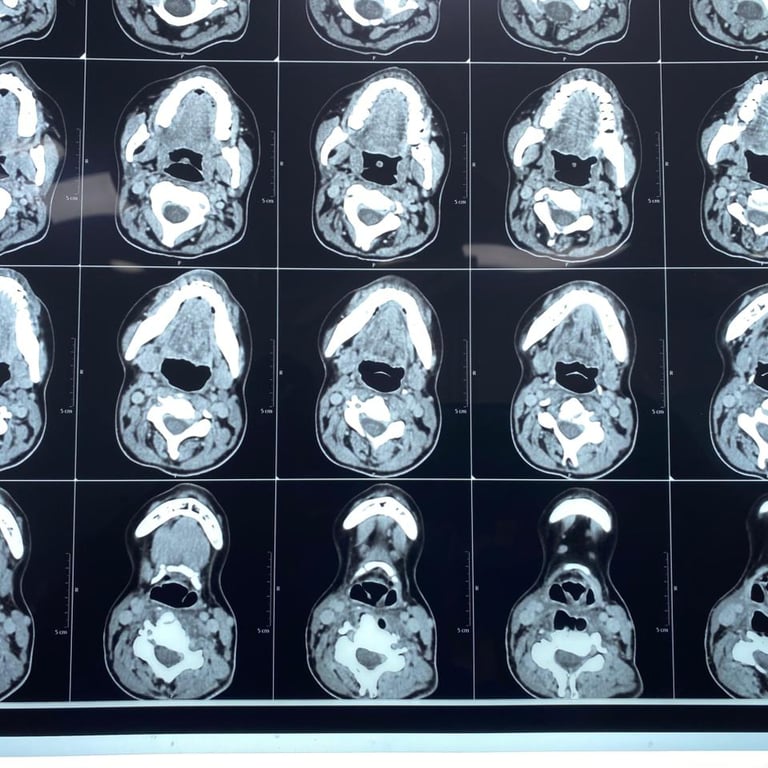

Upon presentation to me, a thorough clinical evaluation was performed, including endoscopic examination and imaging with CT and MRI.

In addition to confirming the chronic pharyngocutaneous fistula, imaging revealed a previously undetected large pharyngeal pouch, contributing to persistent leakage and impaired swallowing. Identifying this concealed pathology was critical to designing a definitive surgical strategy.